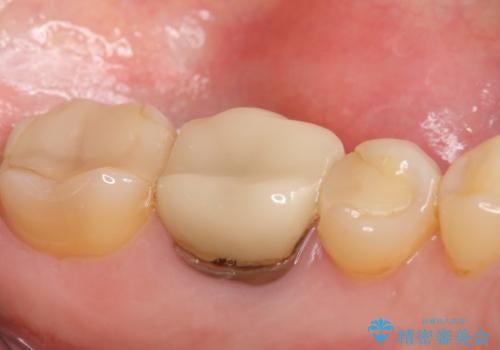

- 左下6の歯で咬むと痛みがあり、たまに膿も出てくるので診て欲しいといらっしゃった方の症例です。

被せ物を外したところ歯が割れており保存不可能だったため抜歯し、インプラントによる欠損補綴を行いました。